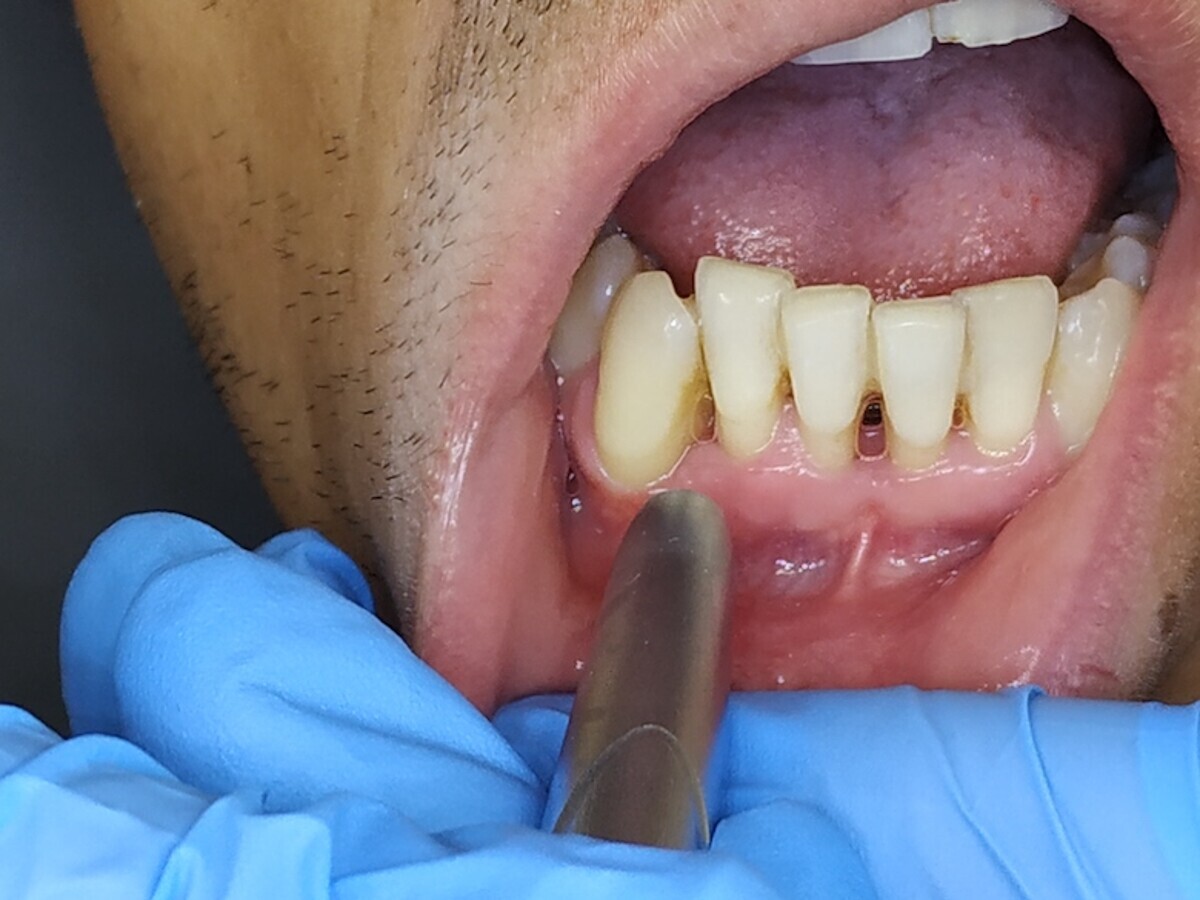

En la cirugía de tejidos blandos, la gingivectomía es probablemente uno de los tratamientos más básicos y que más frecuentemente se realizan en periodoncia quirúrgica (Figuras 17-19). Realizar una gingivectomía con láser es un procedimiento muy sencillo y a la vez bastante rápido que produce un efecto inmediato y que, comparado con una gingivectomía convencional con bisturí, ofrece una serie de ventajas como por ejemplo una hemostasia excelente, lo que mejora la visibilidad del campo y resulta en una molestia postoperatoria mínima para el paciente11.

La gingivectomía con láser es un procedimiento muy rápido y sencillo que ofrece beneficios comparado con una gingivectomía convencional (ver Figuras 17-19).

Fig. 17.

Fig. 18.

Fig. 19. Las figuras 17-19 muestran que la gingivectomía con láser es un procedimiento muy rápido y sencillo que produce un efecto inmediato y ofrece ventajas comparado con la gingivectomía convencional con bisturí.

Cuando el aumento del volumen de los tejidos blandos es grande y generalizado, estos agrandamientos gingivales son medicamentosos, y es en estos casos en los que la utilización del láser presenta ventajas realmente importantes y llamativas frente a la técnica convencional (Figuras 20 y 21).

Fig. 20.

Figuras 20 y 21. Las figuras 20 y 21 indican que en los agrandamientos gingivales voluminosos, la utilización del láser presenta ventajas llamativas frente a la técnica convencional.

Mavrogiannis y colaboradores publicaron un trabajo en el que compararon tres técnicas quirúrgicas diferentes para este tratamiento y concluyeron que la cirugía de colgajo no ofreció ventajas frente a la gingivectomía convencional respecto a recurrencia y que el índice de recurrencia fue significativamente menor en pacientes tratados con láser12.